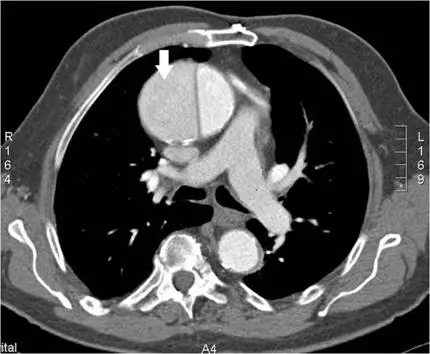

承上題【下圖箭號所指最可能的解剖部位為何?】附圖,箭號所指最可能之診斷為何?

本圖為**胸部電腦斷層血管攝影(CT angiography, CTA)**橫切面影像(縱隔窗)。

主要觀察所見:

- 影像中央可見升主動脈(ascending aorta)明顯擴大

- 升主動脈腔內可見一條白色箭號,指向腔內一道線狀低密度薄片——即內膜瓣(intimal flap),將主動脈管腔分隔為**真腔(true lumen)與假腔(false lumen)**兩個腔室

- 真腔(較小、密度較高,在動脈相早期對比劑充填較亮)與假腔(較大、對比劑充填略延遲)可見明顯區分

- 心包腔周邊可見少量液體(心包積液,可能為出血性),符合 Stanford Type A 剝離的潛在併發症

- 降主動脈截面位於脊椎前方,亦可見,但箭號指向升主動脈病灶

結論: 升主動脈內見內膜瓣,為主動脈剝離的典型影像,累及升主動脈,屬**Stanford Type A(DeBakey Type I/II)**主動脈剝離。